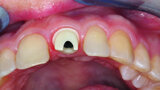

Fig. 1: Single-tooth exposure of tooth #21 after recurrent marginal gingivitis. Owing to the initial diagnosis of extensive resorption, the tooth could not be preserved.

Fig. 8: The resorption of tooth #21, external view. This confirmed the accuracy of the diagnosis from

the imaging procedure.